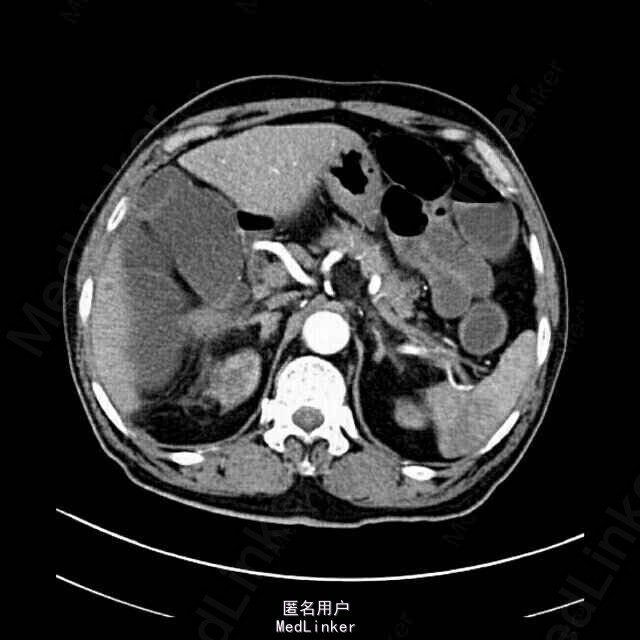

查体:血压:190/110mmHg,巩膜可疑黄染,腹稍膨隆,未见胃肠型及蠕动波,未见腹壁静脉曲张,腹肌软,上腹部压痛明显,无反跳痛,余腹无明显压痛、反跳痛,肝脾肋下未及,墨菲氏征阴性,未及包块,肝肾区无叩痛,移动性浊音阴性,肠鸣音约2-3次/分。 辅助检查:肝功、血脂:AST56U/L,GGT54U/L,LD406U/L,TBA13.9umol/L,AFU61U/L,CHOL6.82mmol/L,HDL1.67mmol/L,LDL4.13mmol/L,APOB1.59g/L。血清胰腺两项:淀粉酶测定165U/L,脂肪酶409U/L。凝血四项:APTT50.1s,TT22.9s。电肾八项:尿素氮9.1mmol/L,肌酐171.5umol/L,葡萄糖14.60mmol/L,CO218.4mmol/L。血常规:白细胞16.00×109/L,中性粒细胞12.72×109/L,红细胞5.52×1012/L,血红蛋白174g/L,HCT0.51,MCH31.6Pg。血沉未见明显异常。胸片+腹平片:心影增大,主动脉硬化。腹部未见气腹及肠梗阻征。彩超提示:1、肝内胆管壁毛糙增厚:考虑肝内胆道感染。2、待排右肾小结石。3、左肾、膀胱、前列腺、脾、胰未见明显异常。4、肠系膜上动脉未见明显异常。全腹平扫+动脉CTA示1、肠系膜上动脉下段及部分分支内可见充盈缺损,分支减少,考虑肠系膜血栓形成可能性大,伴部分小肠缺血改变,请结合临床。2、脾脏小片状低密度影,考虑脾梗塞可能性大,请结合临床。3、考虑不完全性肠梗阻,建议随访。4、目前未见明显腹主夹层动脉瘤,请结合临床。